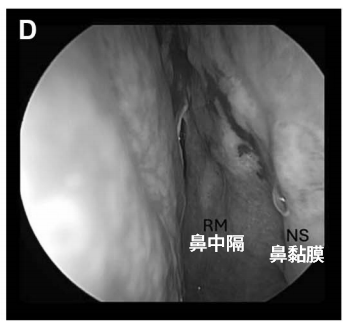

D:蝶竇被顱腔化并以自體脂肪填充,鼻黏膜縫合;腫瘤全切除,未見腦脊液漏。

術后恢復:術后第 1 天即開始下床活動,術后無神經功能障礙、腦脊液漏或感染發(fā)生,1 周后出院。

術后 4 周內鏡復查顯示鼻黏膜縫合處愈合良好,無結痂,患者無鼻部不適主訴。